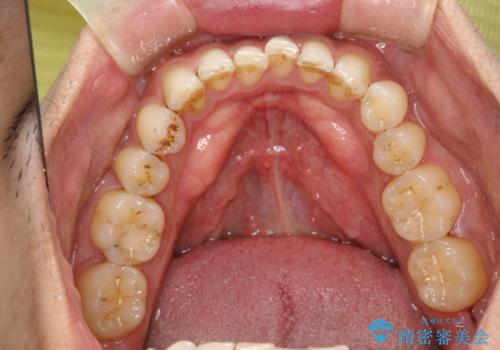

歯と歯の間の着色をPMTCでできる限り除去

- 歯と歯の間の着色を綺麗にしたいとのことで来院されました。PMTC60分で取れる範囲の着色や歯石などの除去を行いました。